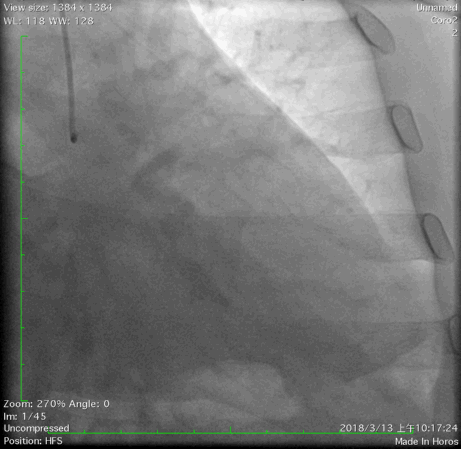

2018年3月13日外院行造影检查示左优势,LAD发出后闭塞,LCX优势型,远端可见与LAD远端形成心外膜侧支,OM1闭塞,RCA闭塞。当地尝试开通RCA和LAD失败,经我院心内、外科联合讨论后,拟心内科介入开通LAD闭塞。

冠脉造影: